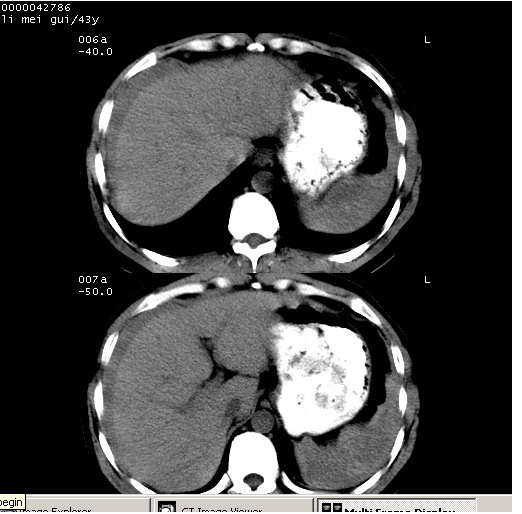

| 患者,男,43岁。突发腹痛2小时,面色苍白,难以平卧。自述近期无明确外伤史,为摩托车驾驶员。 腹部b超检查:脾脏中上极回声异常,肿瘤待排。 临床诊断:腹痛原因待查。 上中腹部ct轴位平扫+增强扫描(层厚10mm,螺距1.0,重建间隔10mm),图像如下: ![]() ![]() ![]() ![]() ![]() ![]() ![]() ![]() ![]() ![]() ![]() ![]() ![]() ![]() ![]() ![]() ![]() ![]() ![]() ![]() ![]() ![]() ![]() ![]() ![]() ![]() ![]() ![]() ![]() ![]() ![]() ![]() ![]() ![]() ![]() zrs发言:支持脾破裂 wwp发言:支持脾破裂并腹水。 xulianj发言:脾脏肿瘤破裂可能性大 zsl6918发言:不像肿瘤出血,考虑还是与外伤后引起的慢性出血有关 zzyy发言:平扫见肝周及脾周积液,脾内密度不均。脾内肿瘤较少见。还是外伤性脾破裂。 沈丘东方医院发言:脾门区一个不均匀强化病灶与其周液体相连多考虑脾占位破裂出血 yixianman001011发言:脾破裂并腹水是可以肯定的,具体原因多以肿瘤性破裂出血,脾脏淋巴瘤可能性大. 结果: 术后,经详细询问患者,其仔细回忆:一月前骑摩托时左侧腰部与别人有“轻微”触碰,因责任在自已,当时又无明显不适,未引起注意。 临床术后诊断:脾破裂并失血性休克(1.外伤性迟发性脾破裂。2.脾脏肿瘤破裂?) 术后标本病检:脾破裂并出血,未见明显肿瘤成份。 原贴地址:http://www.radinet.com.cn/forum_view.asp?forum_id=4&view_id=34070 |